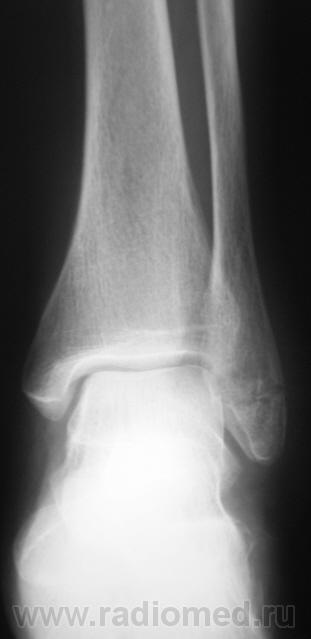

Рискну предположить, что сломана.

ведь сломана.

Значит перелом без смещения отломков?

перелом наружной лодыжки без смещения отломков.

Похоже на перелом лодыжки, есть все признаки, но где то подвох, ведь Валентин Львович банальный перелом лодыжки, которые десятки в день проходят, на сайт бы не выставил